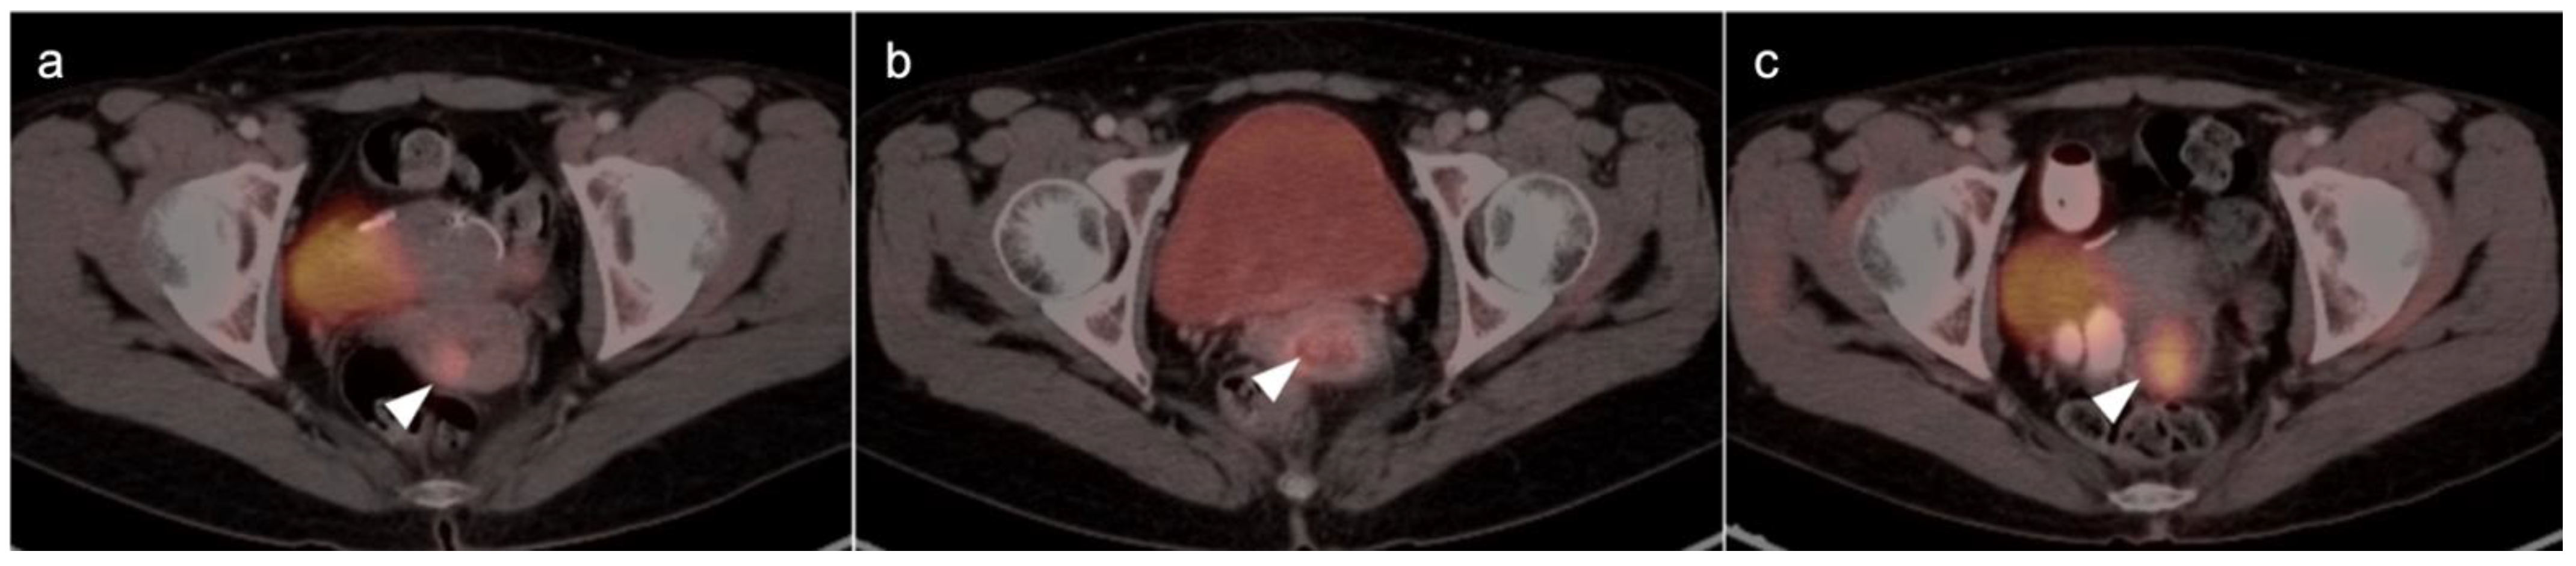

2.4. Cervical Cancer

2.6. Vulvar Carcinoma